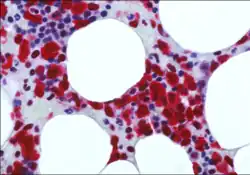

Brunangelo Falini is an Italian hematologist, academic and researcher. He is a Full Professor of Hematology, and Head of the Institute of Hematology and Bone Marrow Transplantation at University of Perugia.[1]

Falini serves as a member of the International Lymphoma Study Group (ILSG) and has been in the Clinical Advisory Committees for the WHO classification of lympho-hemopoietic tumors (2001, 2008 and 2017 versions). He has made discoveries in the field of acute myeloid leukemia (AML) and lymphomas, going from bench to bedside.[2]

Falini's research contributions fall in the area of precision medicine. His scientific activity ranges from the field of monoclonal antibodies for diagnostic and therapeutic purposes to genomic studies on AML and hairy cell leukemia (HCL). His discoveries of NPM1 mutations in AML and BRAF-V600E in HCL, identified new mechanisms of leukemogenesis and resulted into improvement of the diagnosis, prognostic stratification, molecular monitoring and therapy of these hematological malignancies.[2]

In 2005, stemming from his immunohistological studies on ALK-positive ALCL, Falini discovered that tumor cells from about one-third of adult AML (mostly carrying a normal cytogenetic) expressed aberrantly in the cytoplasm nucleophosmin (a nucleolar located protein). This finding prompted Falini and colleagues to sequence the NPM1 gene and to discover heterozygous mutations at exon 12, responsible for the aberrant nuclear export of the NPM1 mutant protein.

Falini's group also demonstrated that NPM1 mutations are AML specific and associated with a de novo origin of the disease.[9] His research team then identified molecular variants of NPM1 mutations (other than exon 12), clarified the molecular mechanisms underlying the ectopic cytoplasmic accumulation of the NPM1 mutants[10] and proposed that it plays a critical role in leukemogenesis. Falini and colleagues also discovered a unique gene expression and microRNA profile of NPM1-mutated AML and demonstrated that over-expression of HOX genes is closely related to the cytoplasmic delocalization of NPM1 mutants.[11]